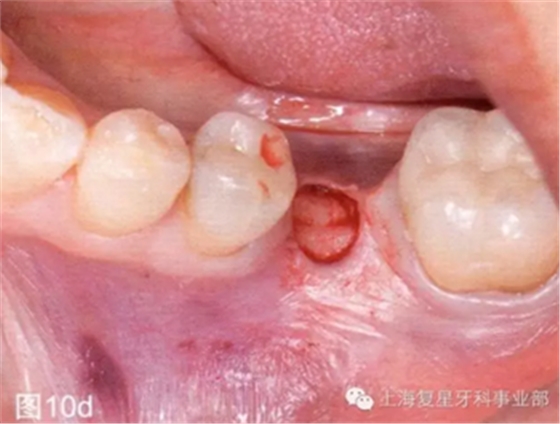

第二天患者就診進(jìn)行手術(shù)。用0.12%葡萄糖酸氯已定漱口水(Oralgene,Laboratorios Maver)含漱2分鐘后,進(jìn)行消毒和術(shù)區(qū)的準(zhǔn)備,在缺牙區(qū)(36#牙區(qū)域)的頰舌側(cè)和頂部進(jìn)行局部麻醉(2%鹽酸利多卡因和1:100000腎上腺素)。幾分鐘后,置入外科導(dǎo)板,在外科導(dǎo)板上的孔洞中置入中空的圓柱形金屬引導(dǎo)管,然后引導(dǎo)軟組織打孔器進(jìn)入,其轉(zhuǎn)速為1200rpm。然后去除引導(dǎo)板,用剝離子去除截面的軟組織,并浸泡在鹽溶液中(圖10b-d)。

圖10c:使用引導(dǎo)性的組織打孔器去除軟組織

圖10d:去除剝離的軟組織